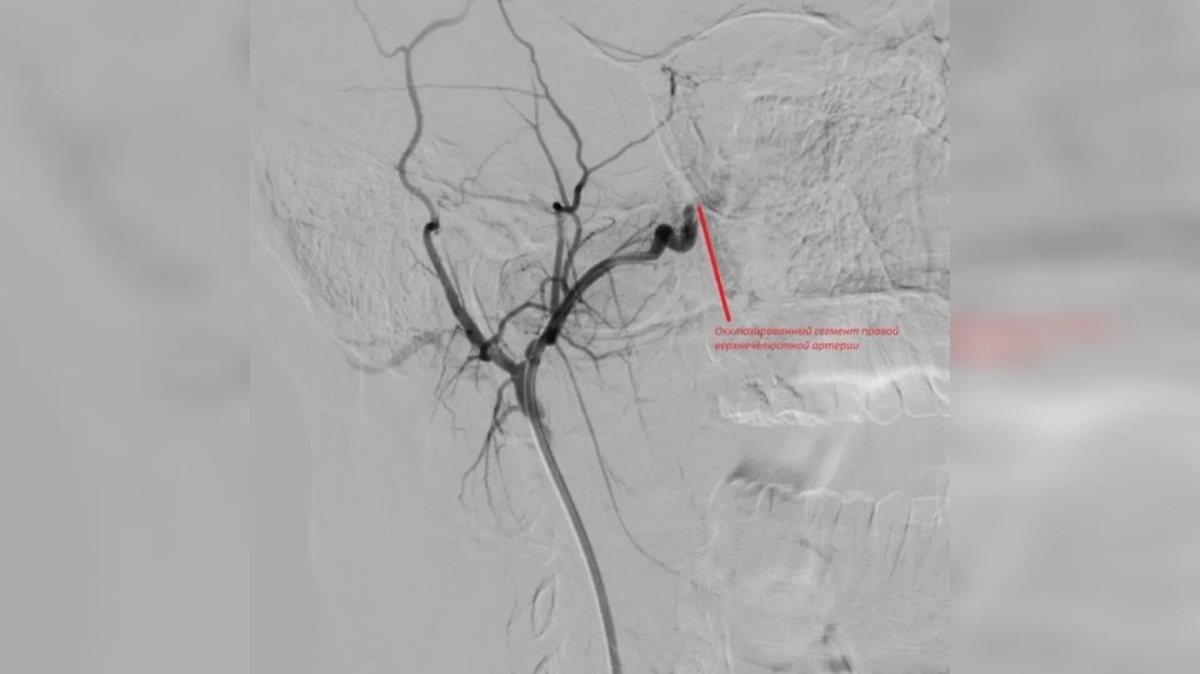

Врачи попытались остановить кровотечение с помощью носового тампона, однако поток крови лишь усиливался. В итоге медики прибегли к хирургическому вмешательству. Источник кровотечения они нашли в дистальных отделах правой верхнечелюстной артерии. После операции пациента выписали домой, больше его ничего не беспокоит.

Сегмент правой верхнечелюстной артерии. Фото © VK / Орловская областная клиническая больница